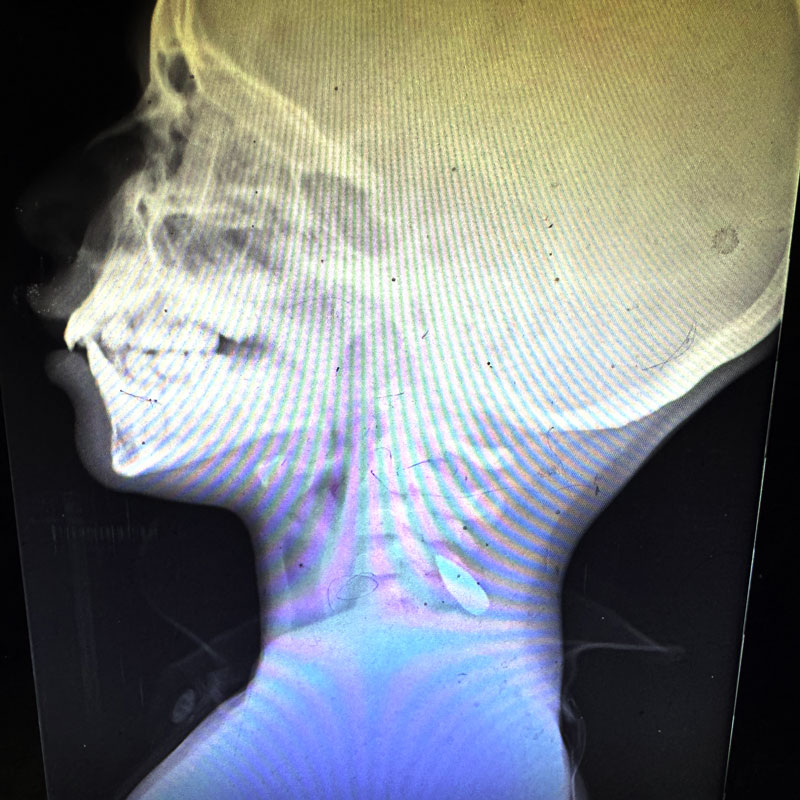

Ces radiographies montrant des enfants de Gaza avec des balles dans le cou ou la tête ont été partagées par le Dr Mimi Syed, qui a travaillé à Khan Younis du 8 août au 5 septembre. Elle a expliqué : « J’ai pris en charge de nombreux jeunes patients, pour la plupart âgés de moins de 12 ans, atteints d’une balle dans la tête ou dans la poitrine, sur le côté gauche. En général, il s’agissait d’une seule balle. Les enfants arrivaient soit déjà morts, soit dans un état critique, et mouraient peu après leur arrivée. »